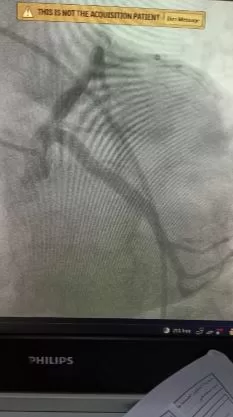

وأُدخلت المريضة غرفة القسطرة القلبية، حيث كشف الفحص التشخيصي عن وجود جلطة بالشريان التاجي تعيق تدفق الدم؛ ليتعامل الفريق الطبي معها ببراعة وينجح في إزالة الجلطة تماماً، مما أدى إلى استقرار الحالة وسريان الدم بصورة طبيعية.